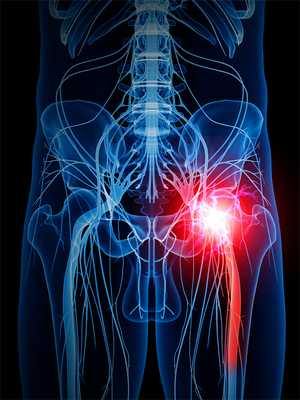

Седалищный нерв - самый большой в нашем организме. Он охватывает большую часть тела - от пояснично-крестцового отдела позвоночника, далее проходит в ягодицу, по задней поверхности бедра и к нижней части ноги. Потому важно следить за его состоянием. Малейшее раздражение в одной части нерва приведет к боли по всему его участку. При отсутствии своевременного лечения постепенно теряется чувствительность и подвижность нижних конечностей.

Воспаление седалищного нерва - дело серьезное, требующее немедленного лечения. Нерв берет начало в зоне малого таза и простирается на территорию большинства отделов нижней части тела. Он охватывает область от поясничного отдела до ступни, а это половина человеческого организма.

Седалищный нерв - крупный периферический ствол волокон. Выходит из крестцового сплетения в районе тазобедренного сустава. Затем проходит между мышцами бедра и в подколенной ямке разделяется на две ветви: большеберцовый и общий малоберцовый нервы [1].

По своим размерам седалищный нерв самый длинный и толстый в организме, в области поясницы выходит из позвоночника, далее через копчик и поверхность таза к ногам. Здесь он разделяется на два пучка, каждый из которых располагается в одной ноге, а нервные окончания доходят до ступней.

В связи с такими анатомическими и функциональными особенностями, боль и различные нарушения чувствительности могут затрагивать не только область поясницы или таза, они распространяются на всю длину ноги.